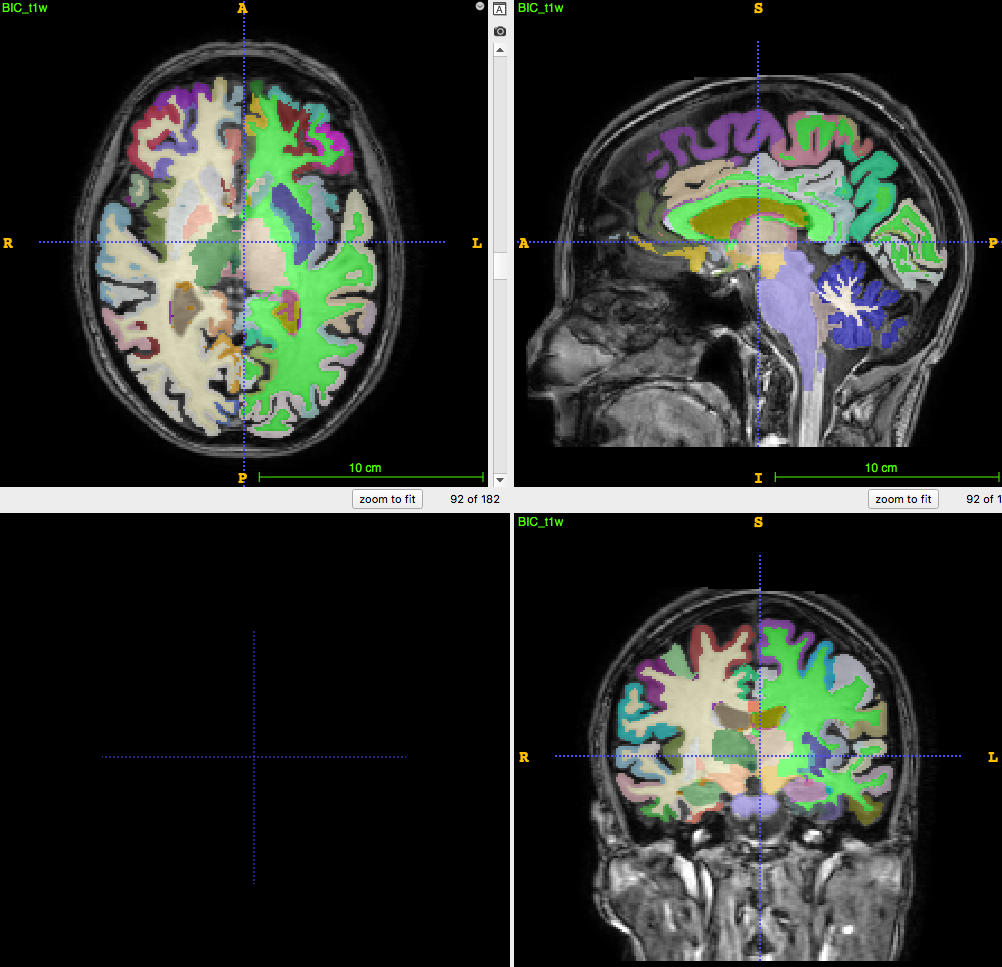

3D T1-weighted MRI:

usually ~1 mm \(^3\) voxel

Segmentation/parcellation at full resolution

PET image:

usually ~8mm \(^3\) voxel

How to apply segmentation?

1. Undersampling T1 segmentation

2. Upsampling PET image